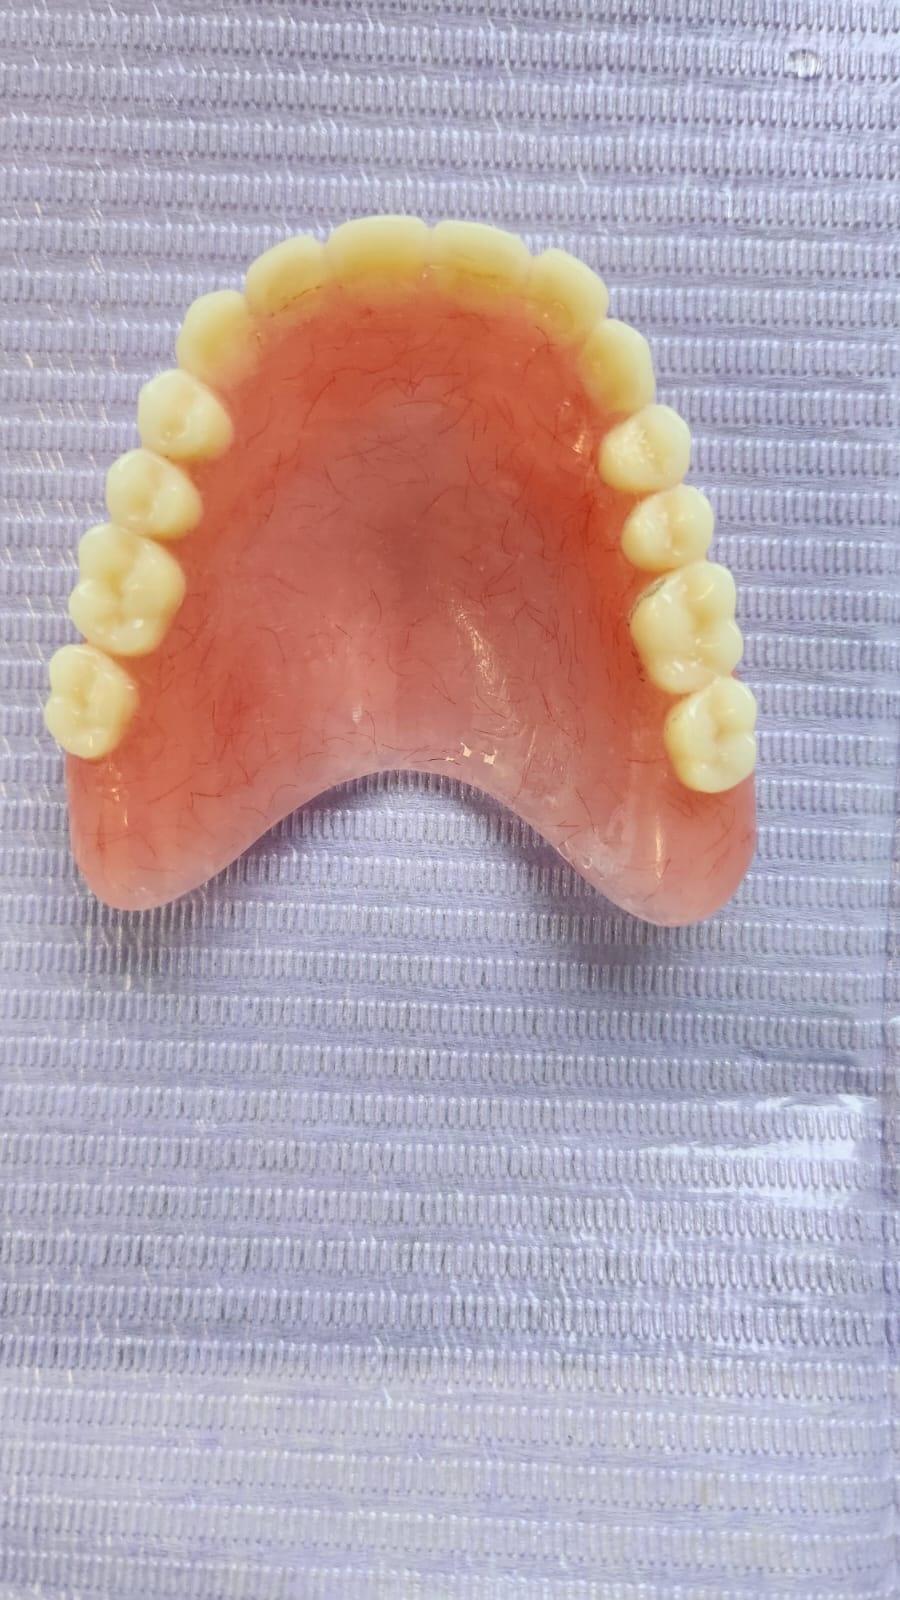

In acest timp are loc procesul de integrare in formatiunea osoasa. Succesul integrarii implantare este dat de catre formarea unei cantitati suficiente de celule osoase in jurul implantului dentar. In functie de necesitatile functionale sau estetice ale pacientului, urmeaza etapa protetica de realizare a lucrarilor de ceramica sau zirconiu. Implantul dentar este foarte important deoarece oasele maxilare se resorb, iar structura fetei incepe sa se modifice. In lipsa dintilor, atat masticatia cat si estetica au de suferit. O igiena necorespunzatoare, fumatul, bruxismul, etc., sunt factori de risc care duc la deteriorarea implantului. In perioada urmatoare dieta pacientului trebuie sa fie moale si la temperatura camerei.

SUPRAPROTEZAREA PE IMPLANT